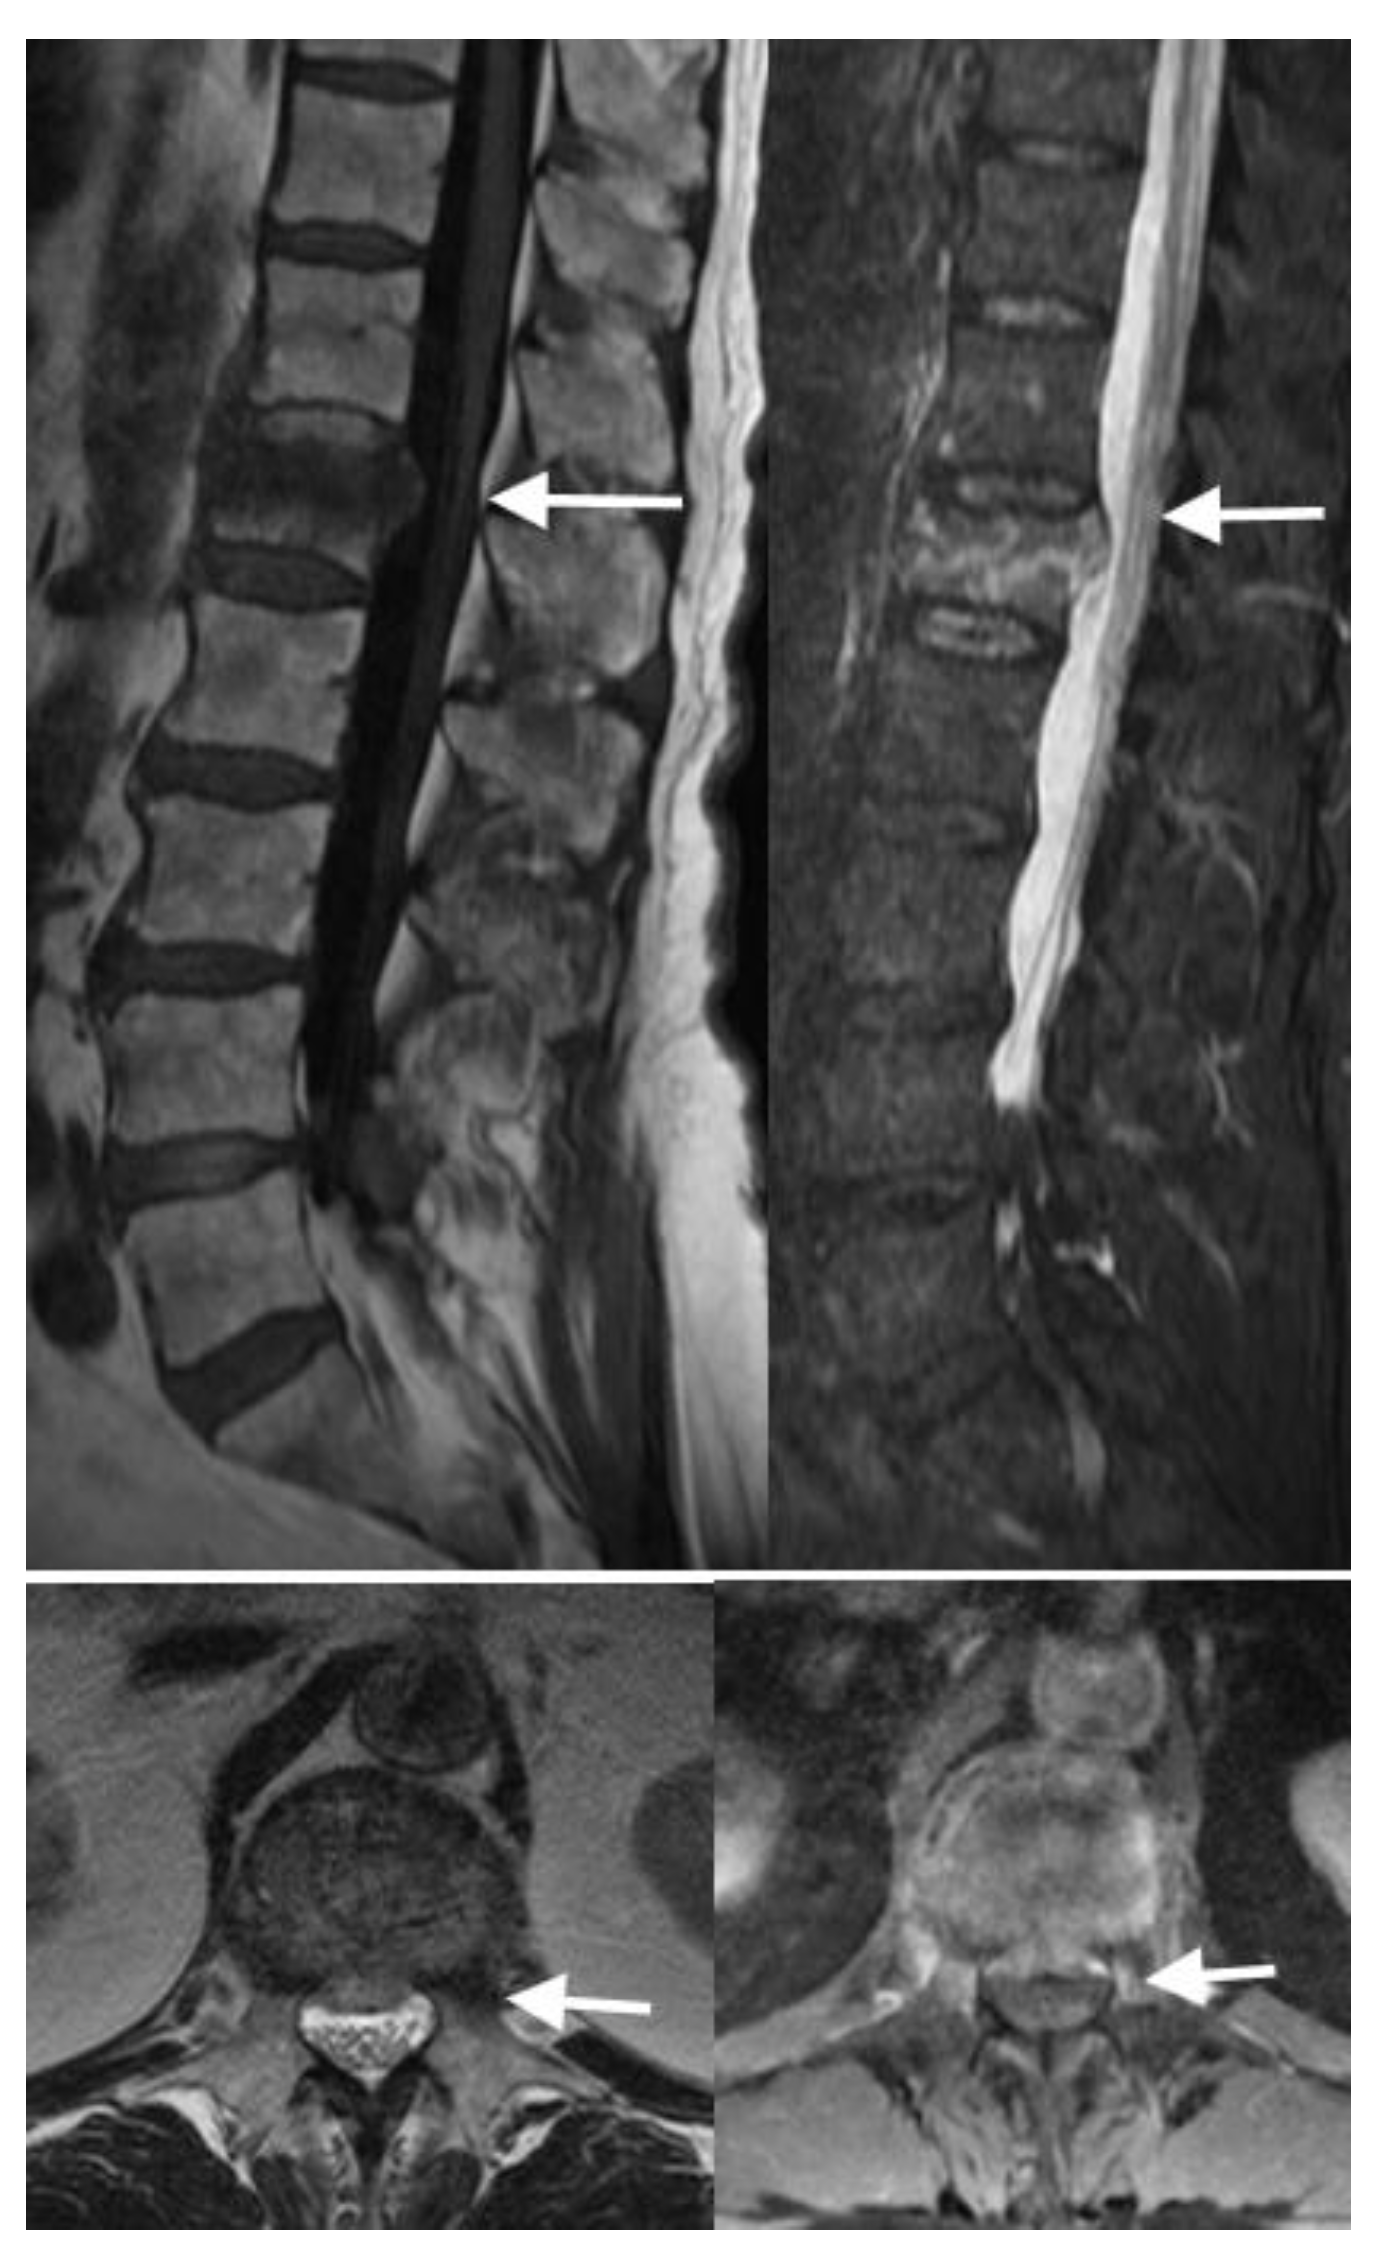

4.3. MRI Scans

4.4. Nuclear Medicine